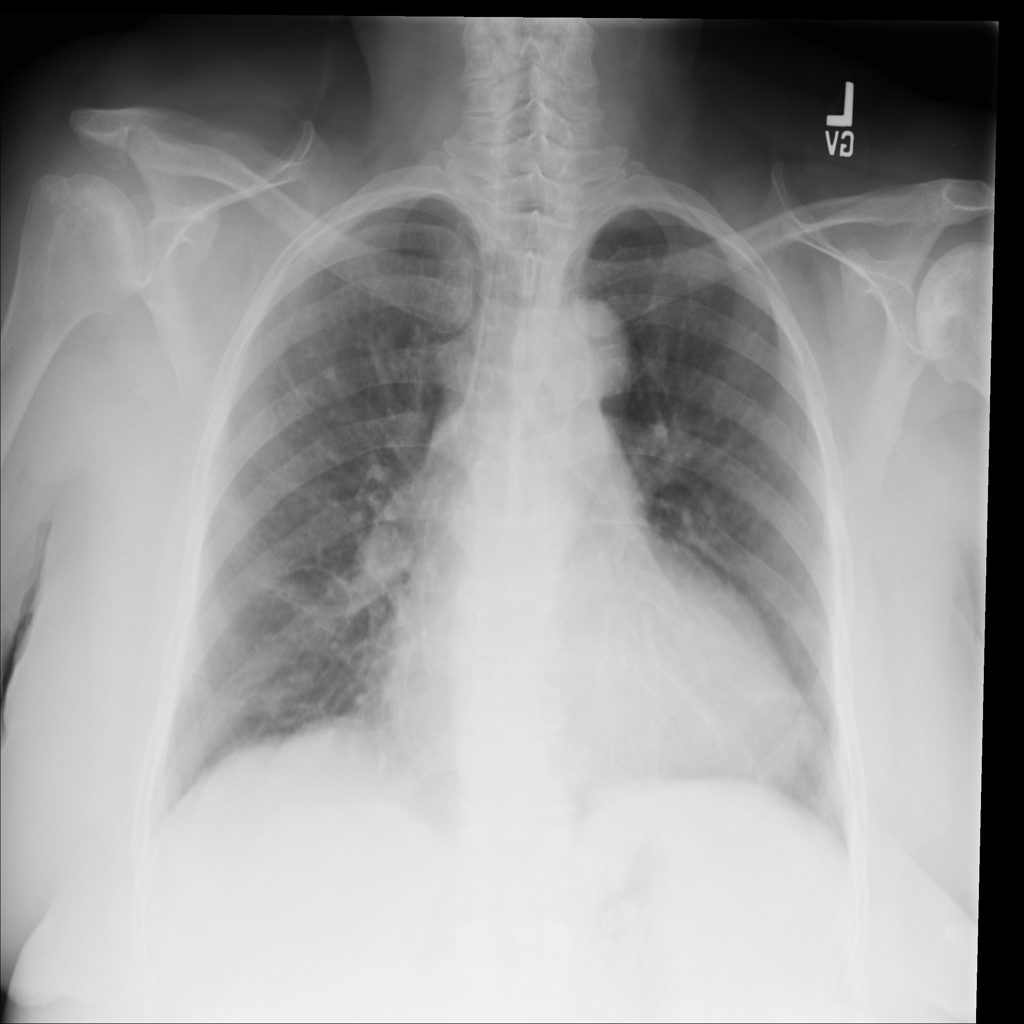

Cardiomegaly

Cardiomegaly means the heart appears enlarged on the chest X-ray. It is a descriptive imaging finding that can be related to heart strain, chronic pressure or volume changes, or even projection effects.

PAT-E36C · IMG-000Cardiomegaly

PAT-E36C · IMG-000

PA